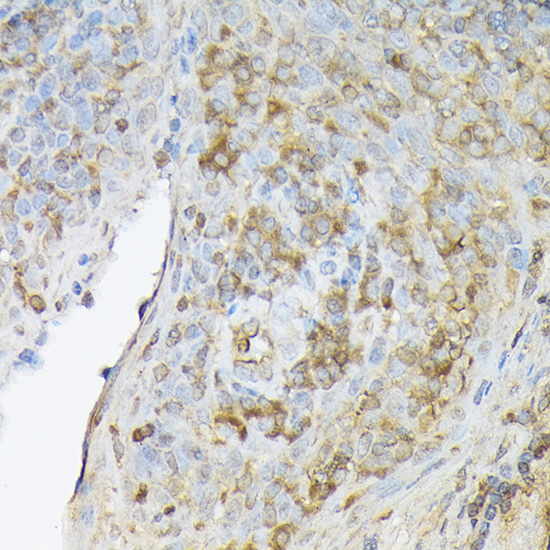

Immunohistochemistry of paraffin-embedded human gastric cancer using CXCL12 Rabbit pAb.

IHC 1:50 - 1:200